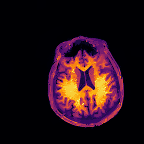

Multi-modality (or multi-channel) imaging is becoming increasingly important and more widely available, e.g. hyperspectral imaging in remote sensing, spectral CT in material sciences as well as multi-contrast MRI and PET-MR in medicine. Research in the last decades resulted in a plethora of mathematical methods to combine data from several modalities. State-of-the-art methods, often formulated as variational regularization, have shown to significantly improve image reconstruction both quantitatively and qualitatively. Almost all of these models rely on the assumption that the modalities are perfectly registered, which is not the case in most real world applications. We propose a variational framework which jointly performs reconstruction and registration, thereby overcoming this hurdle. Numerical results on simulated and real data show the potential of the proposed strategy for various applications in multi-contrast MRI, PET-MR, and hyperspectral imaging: typical misalignments between modalities such as rotations, translations, zooms can be effectively corrected during the reconstruction process. Therefore the proposed framework allows the robust exploitation of shared information across multiple modalities under real conditions.